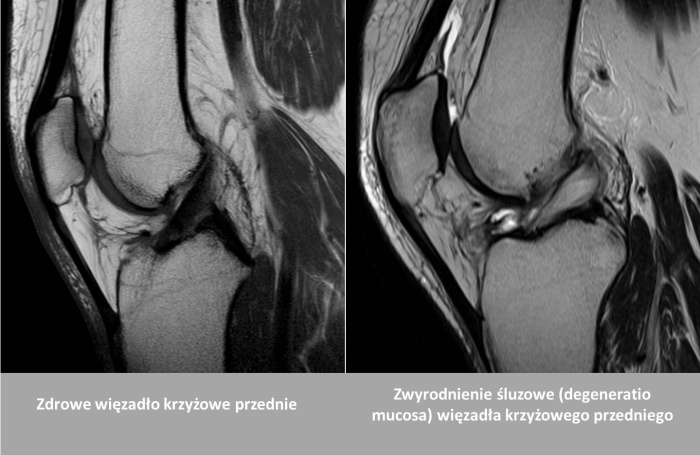

Uszkodzenia więzadeł krzyżowych - leczenie i powrót do aktywności

Więzadła krzyżowe to kluczowe struktury stabilizujące kolano. Dowiedz się, jak leczymy ich uszkodzenia i dlaczego wiek nie jest przeszkodą w rekonstrukcji.